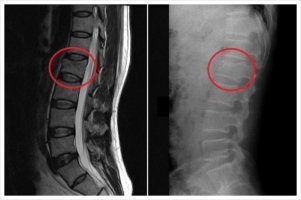

요추압박골절 12번 척추압박골절 흉추12번압박골절 증상

요추압박골절

12번 척추압박골절 허리12번 골절 손목골절 입원 요추압박골절퇴행성